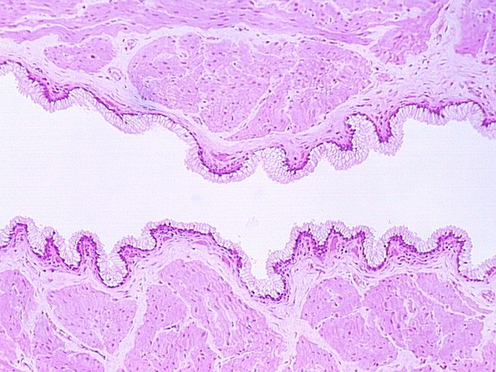

Moving toward the vagina, one can see the abrupt transition between the cervical glands and the stratified squamous epithelium of the vagina. The region showing the vaginal and cervical areas juxtaposed is seen in the following photo.

A low magnification view of the vagina is shown in this photograph. The epithelium is stratified squamous. Underneath the epithelium is a lamina propria. Note that there is no muscularis mucosa. You will use this feature to distinguish the vagina from the esophagus. Another difference is the fact that the vagina has some tight junctions which, along with a lipid secretory material, make the epithelium a permeability barrier.

The vagina wall has no glands and so lubrication must come from the cervix and glands around the opening of the urethra.

The muscle coat in the vaginal wall is interlacing bundles of smooth muscle. There is a thin circumferential band of striated muscle around the ostium of the vagina.

The following figure is from your slide 84, showing a section of the vagina. Note the pale epithelia which are washed out probably because they contain glycogen and lipid.